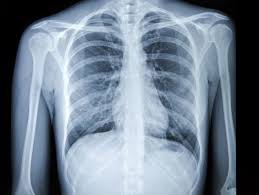

Digital Goa, February, 3 – With the support of AstraZeneca and Qure.AI, over one lakh chest X-rays have been screened across Goa using artificial intelligence, enabling the identification of thousands of critical lung nodules and reducing diagnosis time by more than 50 per cent, informed Health Minister Vishwajeet Rane. Goa is among the first states in the country to scale AI-enabled lung cancer detection across PHCs and CHCs. Govt aims to expand the initiative to over two lakh screenings, said Rane.